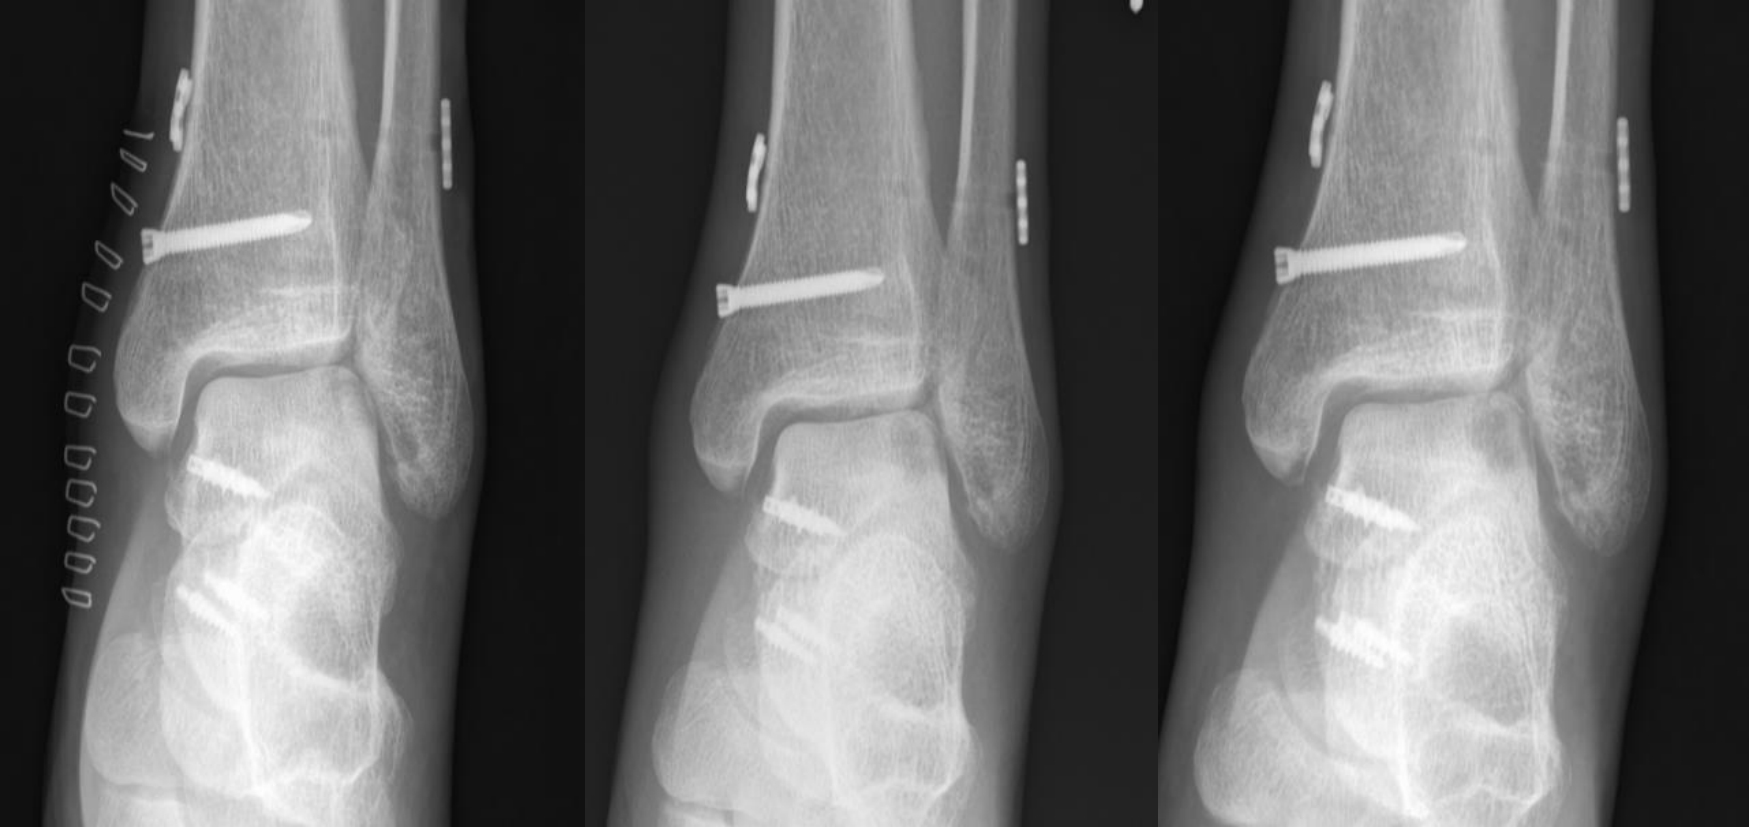

目的 探讨带线锚钉重建三角韧带(deltoid ligament)对踝关节骨折合并韧带损伤患者多维运动功能的影响。 方法 采用回顾性研究方法,纳入2023年3月至2024年3月期间在医院接受切开复位内固定术治疗的DL损伤合并关节骨折患者共210例。根据是否接受三角韧带重建分为重建组(110例)和对照组(单纯骨折固定,100例),其中重建组失访4例,对照组失访2例。比较两组术后优良率,并于术前及术后3、6、12个月评估六自由度(Six Degrees of Freedom,6DOF)运动参数、美国足踝外科协会评分(AOFAS)、疼痛视觉模拟评分(VAS)及影像学指标(间踝间隙和距骨倾斜角),同时记录术后并发症发生率。 结果 重建组手术时间、术中出血量和住院时间均显著高于对照组(P < 0.001)。术后12个月,重建组优良率显著高于对照组(93.40% vs. 81.63%,P < 0.05)。两组术后所有评估指标随时间持续改善,且重建组在踝关节6DOF运动参数(内旋/外旋、背伸/跖屈、内翻/外翻、上移/下移、内移/外移、前移/后移)、AOFAS评分及VAS评分方面改善程度均优于对照组(P < 0.001)。影像学结果显示,重建组间踝间隙及距骨倾斜角恢复更佳(P < 0.001)。两组术后并发症发生率差异无统计学意义(P > 0.05)。 结论 在关节骨折合并三角韧带损伤的治疗中,带线锚钉重建三角韧带可有效改善踝关节运动功能,提高AOFAS评分,减轻疼痛,促进影像学复位,且不增加术后并发症风险,是治疗此类损伤的安全有效方法。

Objective To investigate the impact of deltoid ligament reconstruction using suture anchors on multidimensional motor function in patients with ankle fractures combined with ligament injuries. Methods A retrospective cohort study included 210 patients undergoing open reduction and internal fixation (ORIF) for ankle fractures with confirmed DL injuries between March 2023 and March 2024. Based on intraoperative management of the DL, patients were allocated to a reconstruction group (received suture anchor-based DL reconstruction, n = 110; 4 lost to follow-up) or a control group (ORIF alone without DL reconstruction, n = 100; 2 lost to follow-up). Outcomes assessed preoperatively and at 3, 6, and 12 months postoperatively included: 6DOF ankle motion parameters (internal/external rotation, dorsiflexion/plantarflexion, inversion/eversion, superior/inferior translation, medial/lateral translation, anterior/posterior translation), American Orthopaedic Foot & Ankle Society (AOFAS) scores, visual analogue scale (VAS) pain scores, and radiographic parameters (medial clear space, talar tilt angle). Clinical efficacy at 12 months and postoperative complication rates were also compared. Results The reconstruction group demonstrated significantly longer operative times, greater intraoperative blood loss, and longer hospital stays compared to the control group (all P < 0.001). At 12-month follow-up, the excellent and good rate (based on AOFAS) was significantly higher in the reconstruction group (93.40% vs. 81.63%, P < 0.05). While all parameters improved significantly over time in both groups, the reconstruction group exhibited significantly greater improvements in all 6DOF motion parameters, higher AOFAS scores, and lower VAS scores at all postoperative time points (all P < 0.001). Radiographically, the reconstruction group achieved significantly better restoration of the medial clear space and talar tilt angle at all postoperative assessments (all P < 0.001). Postoperative complication rates did not differ significantly between the groups (P > 0.05). Conclusion For patients with ankle fractures combined with deltoid ligament injuries, suture anchor-based anatomical reconstruction of the deltoid ligament effectively restores multidirectional ankle kinematics, improves functional outcomes as measured by the AOFAS score, alleviates pain, and facilitates radiographic reduction, without increasing the risk of postoperative complications, thereby representing a safe and effective treatment strategy.